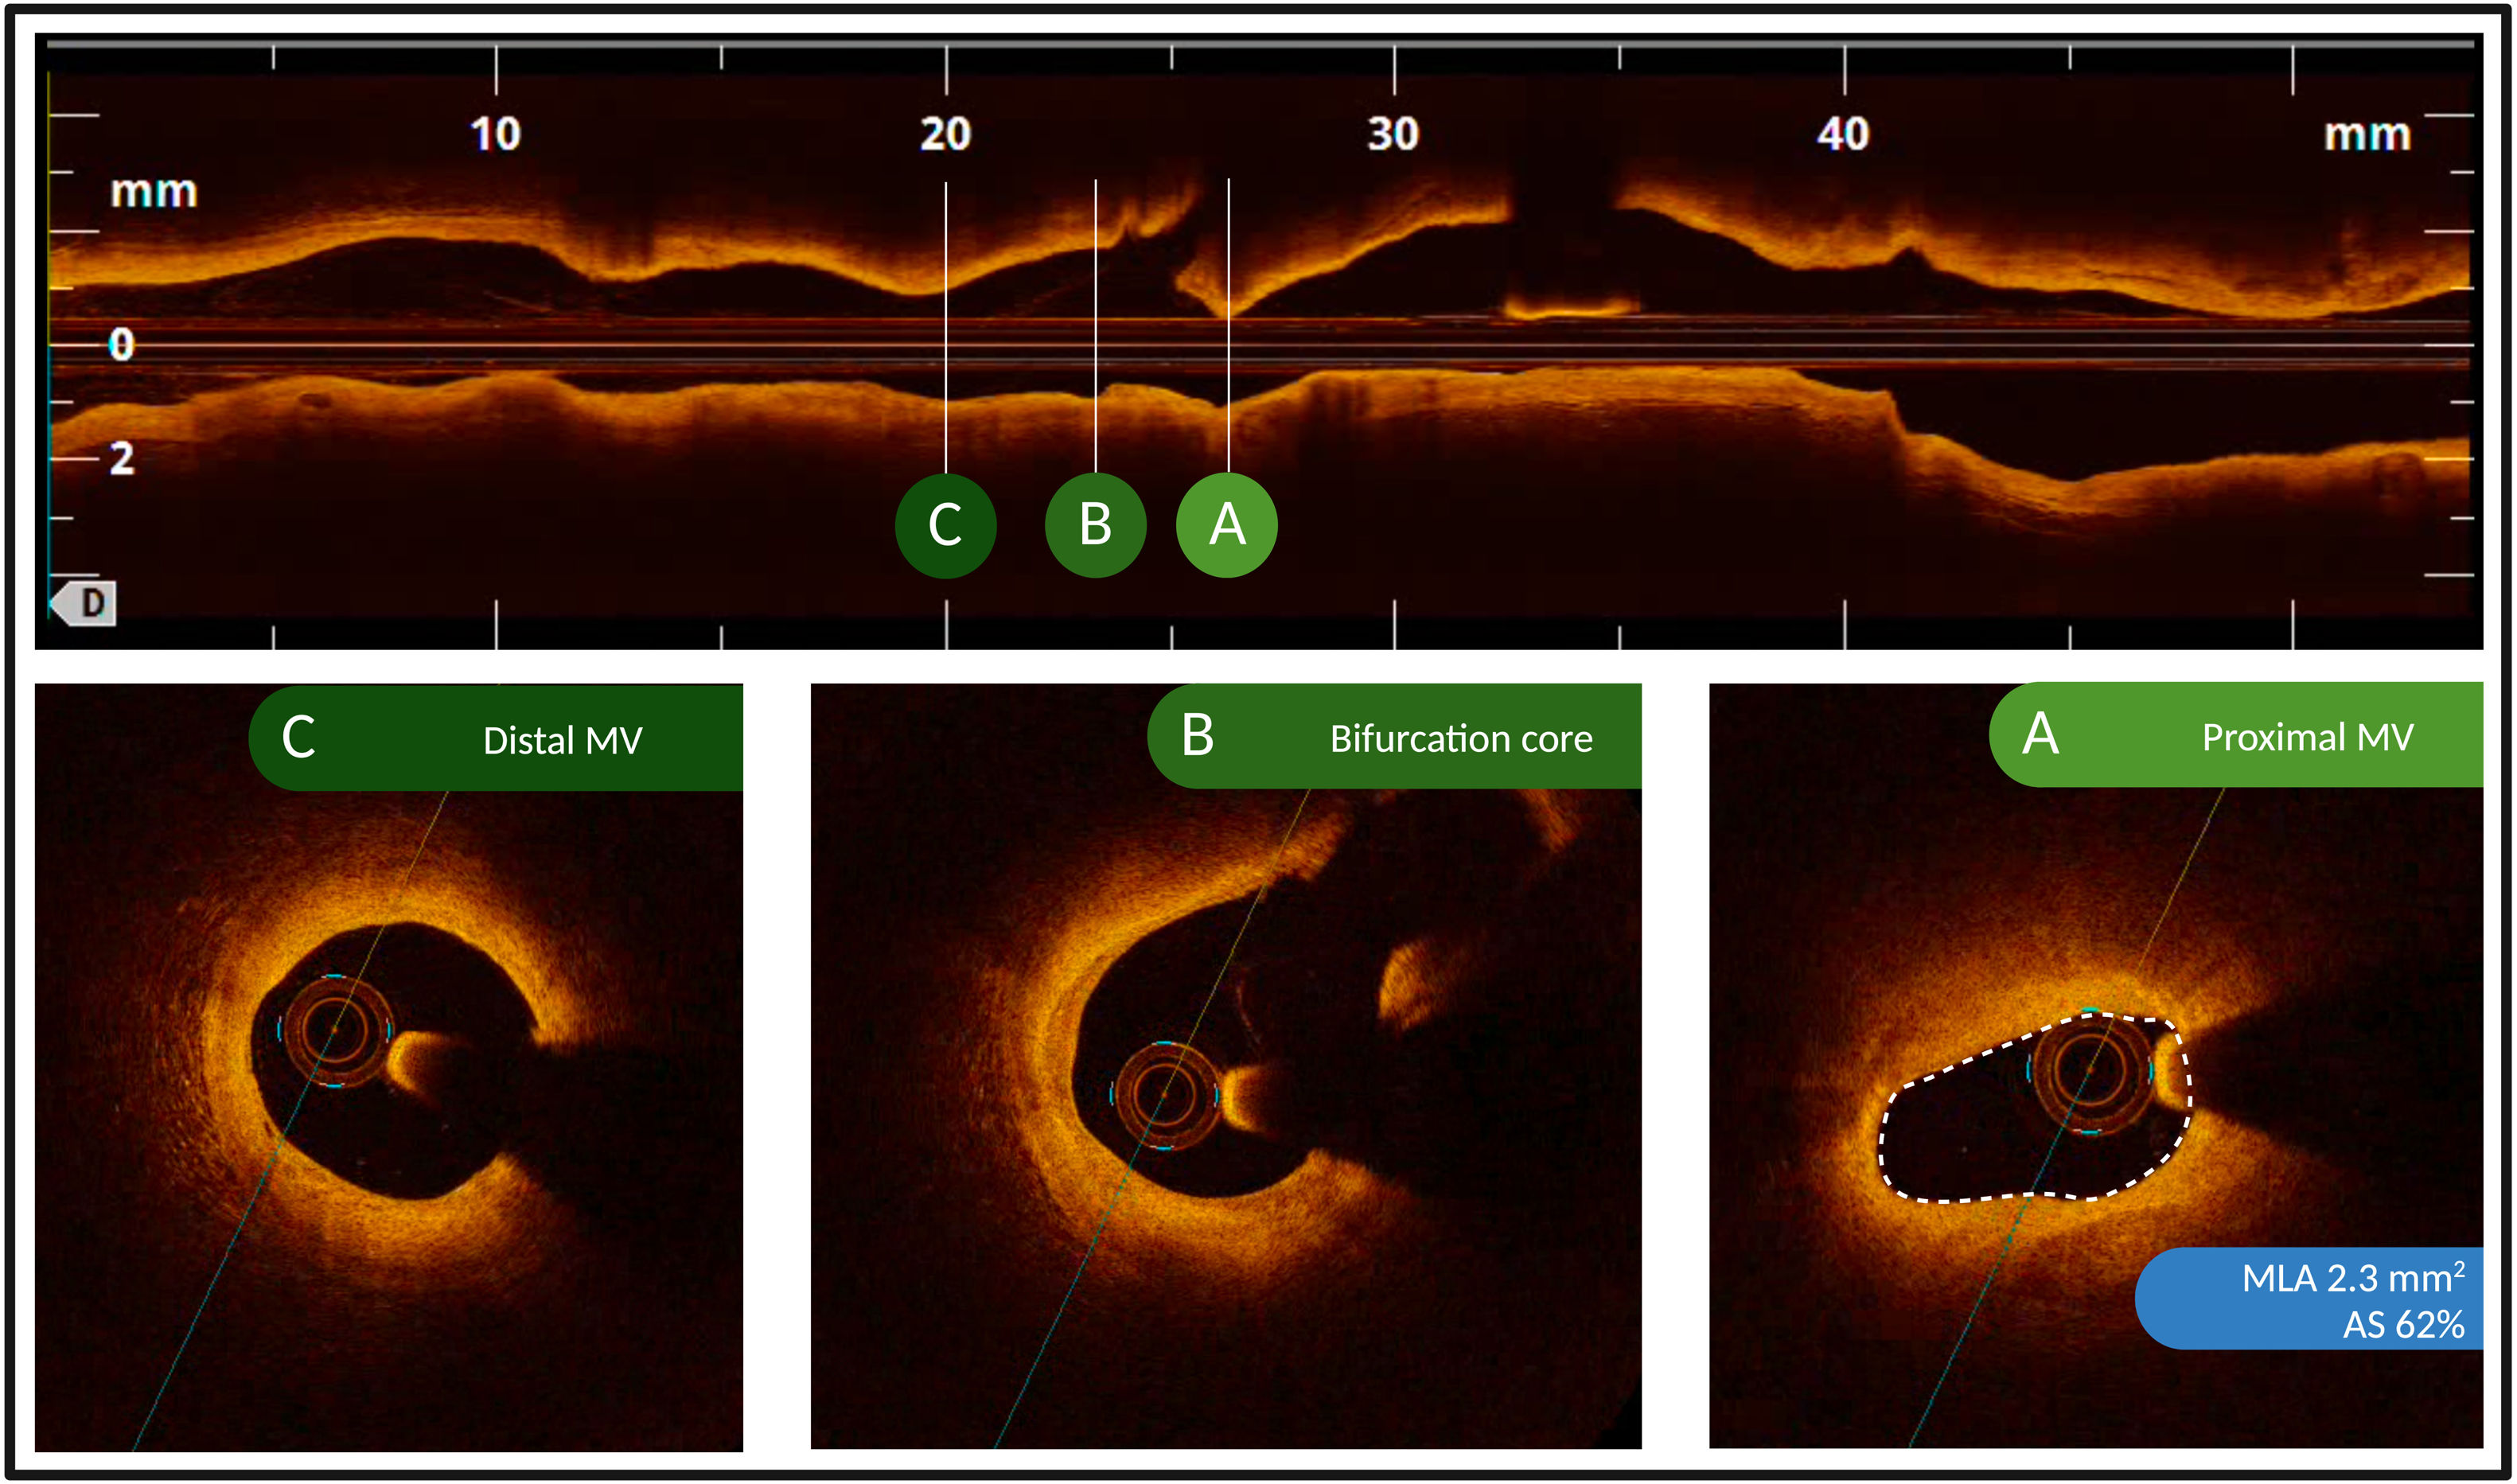

The baseline vessel characteristics are reported in table 2. Vessels with complex lesions were more frequently located in the left anterior descending artery (75.9% vs 55.8%; P<.001) and were more likely to undergo PCI (48.1% vs 29.3%; P<.001) than vessels with noncomplex lesions. Among vessels with complex lesions, 55 (25.9%) had a long lesion (of which 37 [67.3%] were treated with PCI), 53 (25.0%) had a severely calcified lesion (of which 20 [37.7%] were treated with PCI), and 169 (79.7%) had a bifurcation lesion (of which 85 [50.3%] were treated with PCI) (). The OCT graphical representation of the most common complexity criterion, along with the most frequent OCT criterion for performing PCI, is shown in figure 1.

OCT representation of the most common angiographic complexity and PCI criteria. Bifurcation was the most common angiographic complexity criterion, while an AS of 50%-75% with an MLA <2.5 mm2 was the most frequent criterion for PCI in the OCT arm. The illustrated case shows a bifurcation of the LAD-D1, with a lesion mainly affecting the proximal main vessel, an AS of 62%, and an MLA of 2.3 mm2. AS, area stenosis; D1, first diagonal branch; LAD, left anterior descending artery; MLA, minimal lumen area; MV, main vessel; OCT, optical coherence tomography; PCI, percutaneous coronary intervention.